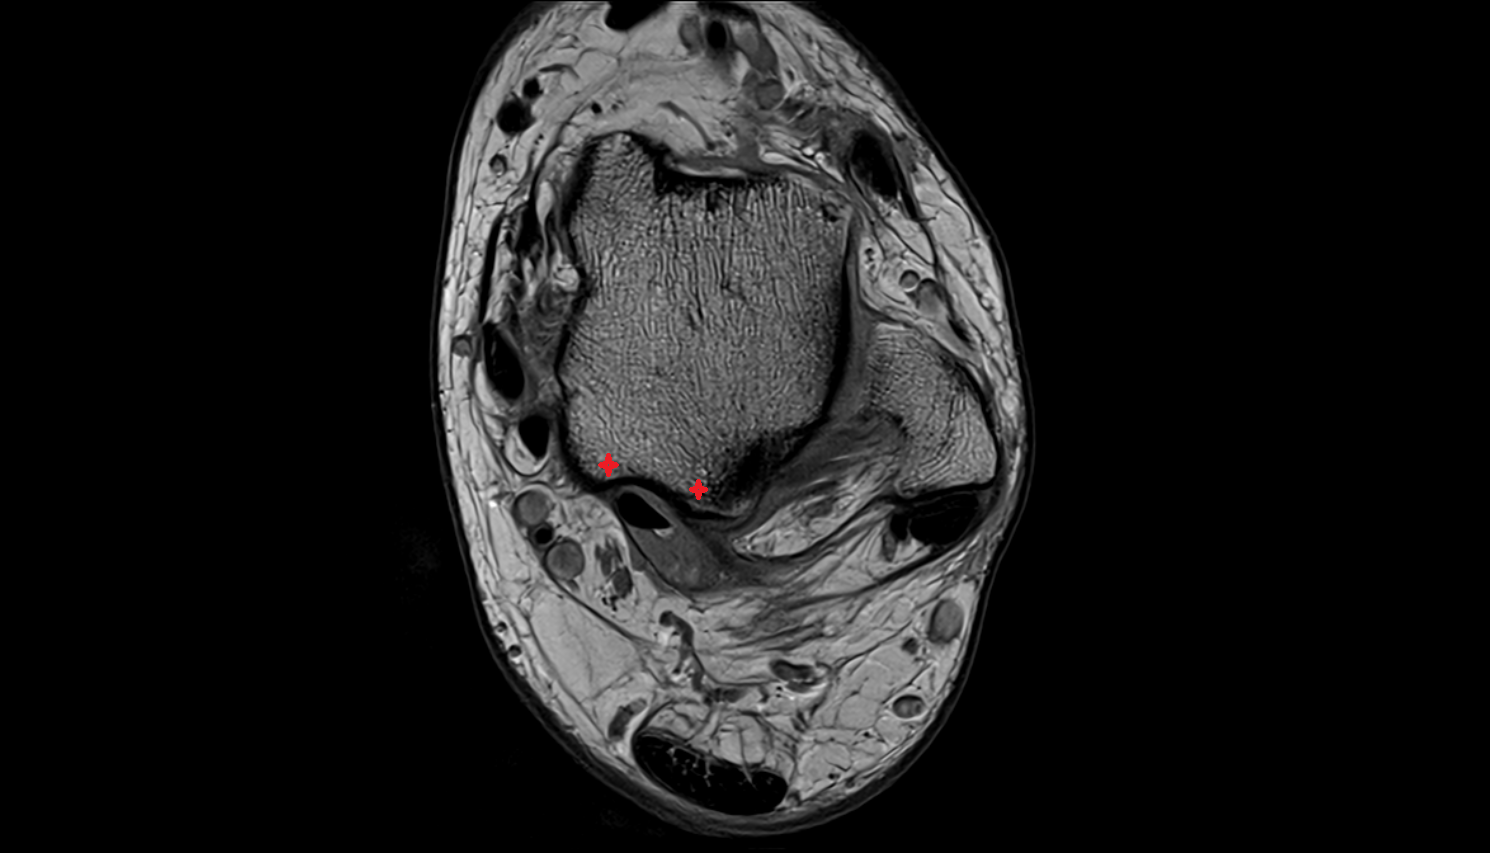

- Talus

- Body of talus

- Calcaneus

- Sustentaculum tali

- Medial malleolus

- Lateral malleolus

- Ankle joint

- Talocalcaneal joint

- Tibialis posterior muscle

- Flexor digitorum longus muscle

- Flexor hallucis longus muscle

- Tibialis posterior tendon